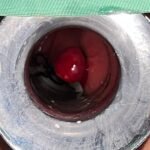

LASER LIAS FOR ANAL FISSURES AND BANDING OF HEMORRHOIDS